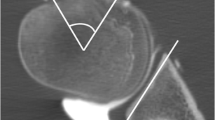

Images were analyzed for the presence of bony Bankart lesions and Hill-Sachs defects. Furthermore, the images were analyzed for further osseous pathologies including scapula fractures, subchondral cysts, calcific tendonitis, and degenerative changes of the AC-joint. The percentage of glenoid bone loss was evaluated in participants with bony Bankart lesions using the best fit model on sagittal images [22]. A circle was drawn using the anterior, posterior, and inferior margin of the glenoid surface as outer boundary and the percentage of bone loss was calculated by dividing the width of the anterior bone loss with the diameter of the circle (Fig. 1). Additionally, anterior glenoid loss leads to a loss of the convexity of the anterior glenoid which was evaluated by drawing and measuring an anterior straight line [23]. The humerus was assessed for Hill-Sachs lesions and in patients with a bipolar lesion, the glenoid track was calculated as previously reported (Fig. 2) [24]. Fractures of the humeral head were graded according to the international AO and Neer classification (Fig. 3) [25, 26]. Furthermore, the glenoid bone width was measured in the sagittal plane.

Evaluation of the glenoid bone loss using the best fit method on a sagittal CT-like UTE image (A) and conventional CT (C). A circle was drawn by one reader along the posterior, anterior, and inferior margin of the glenoid surface, and the percentage of bone loss was calculated by dividing the width of the anterior bone loss with the width of the circle. The glenoid track is calculated as 0.83 D − d, in which D represents the diameter of the intact glenoid in millimeters and the d corresponds to the amount of glenoid bone loss in millimeters [24]. In this case, the glenoid bone loss was 8.75 % (B and D). The anterior straight line measuring the loss of convexity of the anterior glenoid surface after shoulder dislocation with a bony Bankart lesion. A very strong correlation with CT measurements was found in this case (r = 0.97)